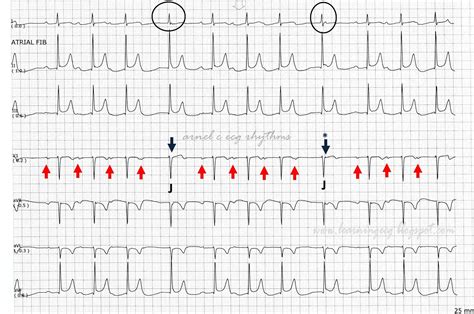

Physicians identify a Junctional Escape Rhythm through specific patterns observed on an electrocardiogram (ECG). Because the electrical impulse originates in the AV junction rather than the SA node, the sequence of atrial and ventricular depolarization is altered, creating a distinct visual signature on the tracing.

• Heart Rate: The rhythm typically maintains a steady rate of 40–60 beats per minute. If the rate exceeds 60 beats per minute, it is classified as accelerated junctional rhythm.

• P-Wave Characteristics: P-waves are often absent, inverted, or appear just after the QRS complex because the atria are depolarized in a retrograde (backward) fashion from the junction.

• QRS Complex: Since the electrical impulse travels through the normal ventricular conduction pathways (the bundle of His and Purkinje fibers), the QRS complex remains narrow, indicating a supraventricular origin.